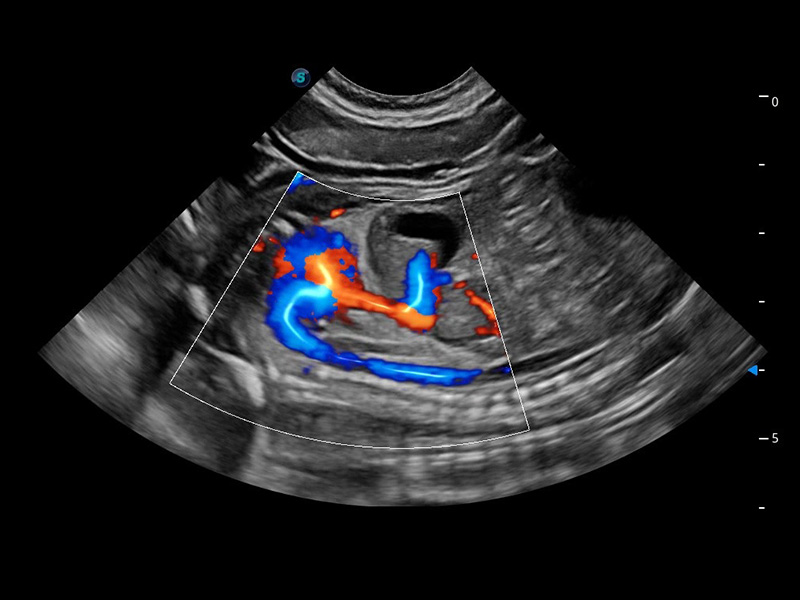

ProPet 60 作為一款高端臺(tái)式動(dòng)物超聲設(shè)備,為動(dòng)物醫(yī)生的日常診斷提供了一系列貼合動(dòng)物臨床需求、解決臨床實(shí)際問題的高級成像功能。憑借全系列高清探頭,滿足醫(yī)生對腹部、心臟、生殖、淺表、肌骨等成像的所有需求,切實(shí)幫助您提升檢查效率,提高診斷信心。